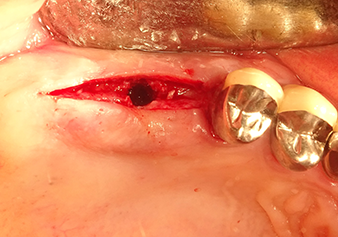

Lo strumento I2A (diametro 2,0 mm) è stato quindi impiegato per perforare il pavimento sinusale in modo graduale e su superfici molto ridotte. Tale metodo piezochirurgico previene il danneggiamento della membrana di Schneider. Durante l'utilizzo di Z25P, la membrana risultava già essere leggermente sollevata dal fluido di raffreddamento fornito attraverso la punta dello strumento (Fig. 3). La quantità di fluido di raffreddamento presente era solo del 50% per evitare che la sede dell'impianto registrasse un'elevata pressione.

Preparazione e accrescimento della sede dell'impianto